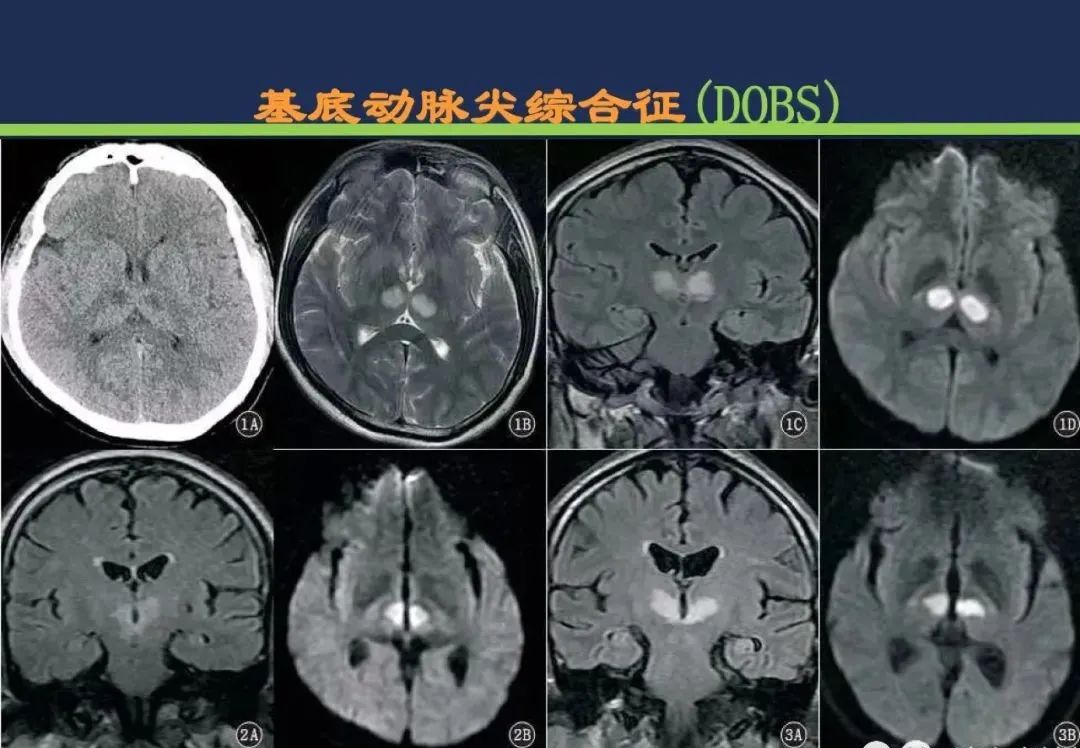

基底动脉尖